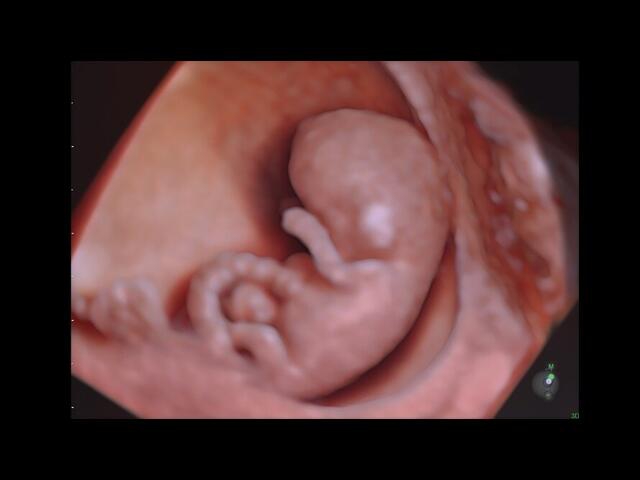

• HDlive: Технология HDlive обеспечивает анатомический реализм и высокую точность диагностики, позволяя совмещать несколько независимых источников света для создания оттенков и теней.

• SonoRenderLive возможность активации функции автоматического определение плода в режиме 3D ;

• Возможность оснащения инновационной опцией для объемной визуализации HDlive Silhouette;